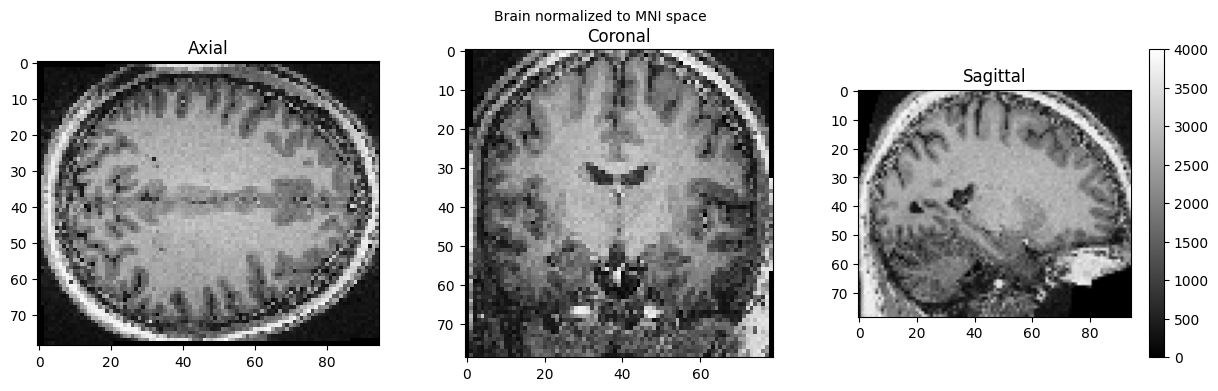

brain_full = nib.load('./wsub-01_ses-01_7T_T1w_defaced.nii').get_fdata()

view_slices_3d(brain_full, slice_nbr=50, vmin=0, vmax=4000, title='Brain normalized to MNI space')